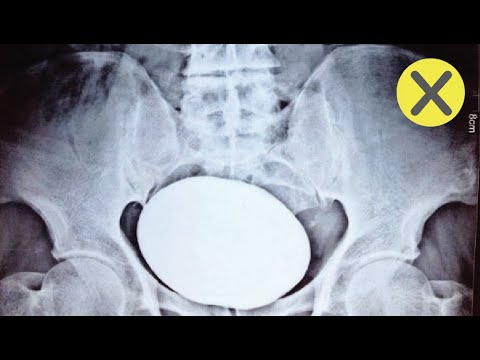

Muchos soñamos con romper un récord mundial y ser conocidos como el mejor en alguna disciplina, Quien no quisiera tener el récord de la persona mas flexible del planeta o SER CONOCIDO COMO LA PERSONA MAS FUERTE DEL MUNDO, Sin embargo existen otros récords que ha nadie le gustaría tener, pero aun así le pertenecen a algunas personas.

Descubre: 10 Records mundiales que no quisieras tener